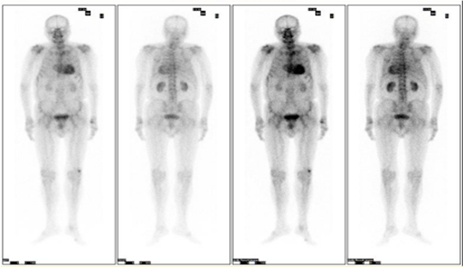

此次确诊的省内首例转甲状腺素蛋白心脏淀粉样变(ATTR-CA)患者为80几岁的王某(化名),因反复慢性心衰伴心律失常多年到我院就诊。入院后该患者的心脏彩超提示心肌肥厚,进行心脏核磁共振扫描结果提示心肌淀粉样变,接诊的干部特诊一科陈建康主任医师联合多学科为患者展开相应排查,使用了包括血清、基因检测、核素、核磁等一系列精准的诊断手段,抽丝剥茧、层层深入,最后诊断患者为野生型ATTR心脏淀粉样变性(ATTRwt),为后续的治疗提供了准确的依据。

▲病例心肌核素99mTc-PYP显像结果